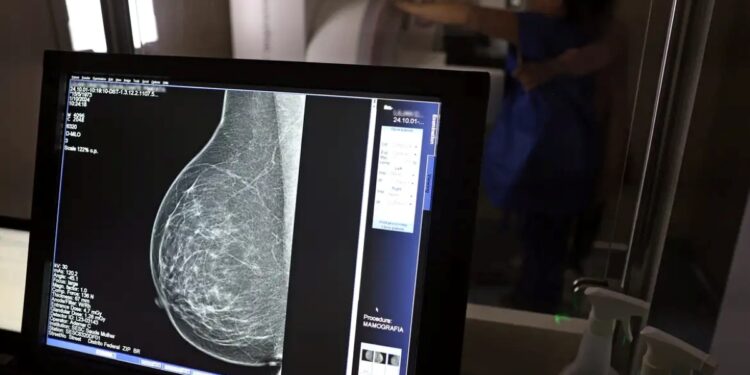

Desperte a atenção para uma oportunidade fundamental de cuidado com a saúde da mulher. Um mutirão irá disponibilizar 140 exames de mamografia todos os dias, proporcionando acesso gratuito ao diagnóstico precoce do câncer de mama em uma ação especial de saúde.

Durante o mês de outubro, uma parceria estratégica entre a Mansão do Caminho e a Secretaria Estadual da Saúde (Sesab) integra a campanha Outubro Rosa, ampliando a oferta de exames de mamografia com ênfase no cuidado, acolhimento e esperança.